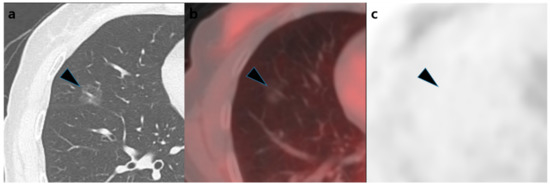

| Visual analysis of [18F]FDG PET/CT | 0.001 * | ||||

| Positive | 22 (88%) | 4 (44%) | 1 (17%) | 27 (68%) | |

| Semi-quantitative analysis of [18F]FDG PET/CT | |||||

| SUVmax | 1.3 (1.1–1.8) | 1.1 (0.7–1.8) | 0.6 (0.5–0.9) | 1.3 (0.8–1.8) | 0.033 * |

| SUVmaxTF | 2.6 (2.2–3.1) | 2.2 (1.9–2.9) | 1.6 (1.5–1.7) | 2.4 (1.9–3.0) | 0.018 * |